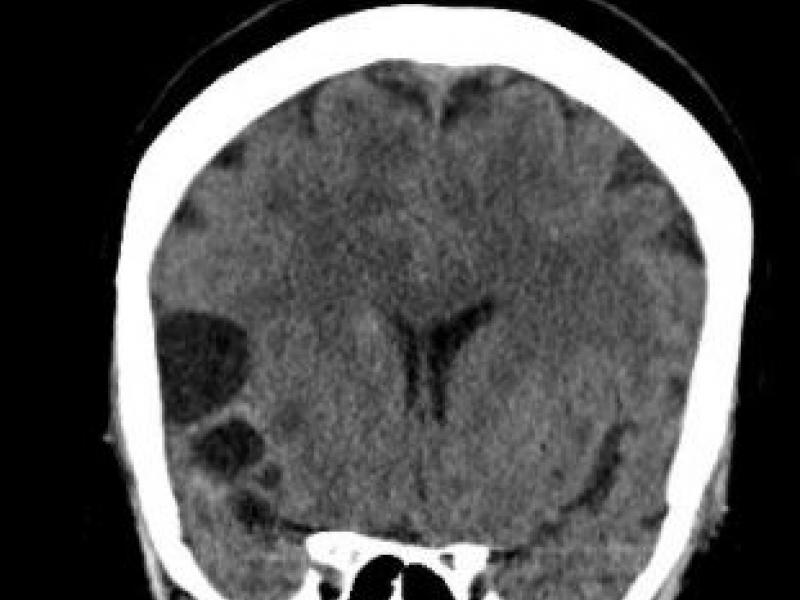

What's the Diagnosis? By Dr. Abby Renko

A 56 yo F w/ hx of DM originally from Mexico presents to the